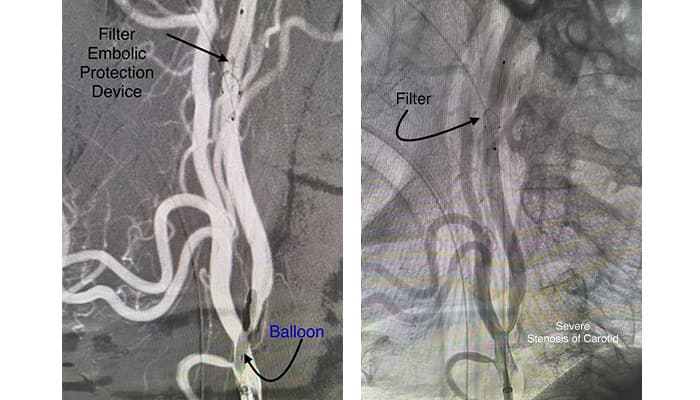

Digital Subtraction Angiography (DSA) was performed to identify the extent of the stenosis. Digital Subtraction Angiography (DSA) confirmed severe carotid artery stenosis. Early diagnosis saved crucial time and played a key role in protecting the patient’s life.

Under Dr. Arindom Kakati’s clinical guidance, a multidisciplinary treatment plan was initiated.The patient was shifted to the advanced Cath Lab for urgent vascular intervention.Carotid Artery Stenting was successfully performed in the Cath Lab by Dr. Gorky Medhi (Interventional Neuroradiology) as part of the coordinated care strategy.